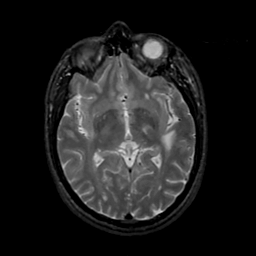

MR Study #20 October 6, 1991 -- Slice #24